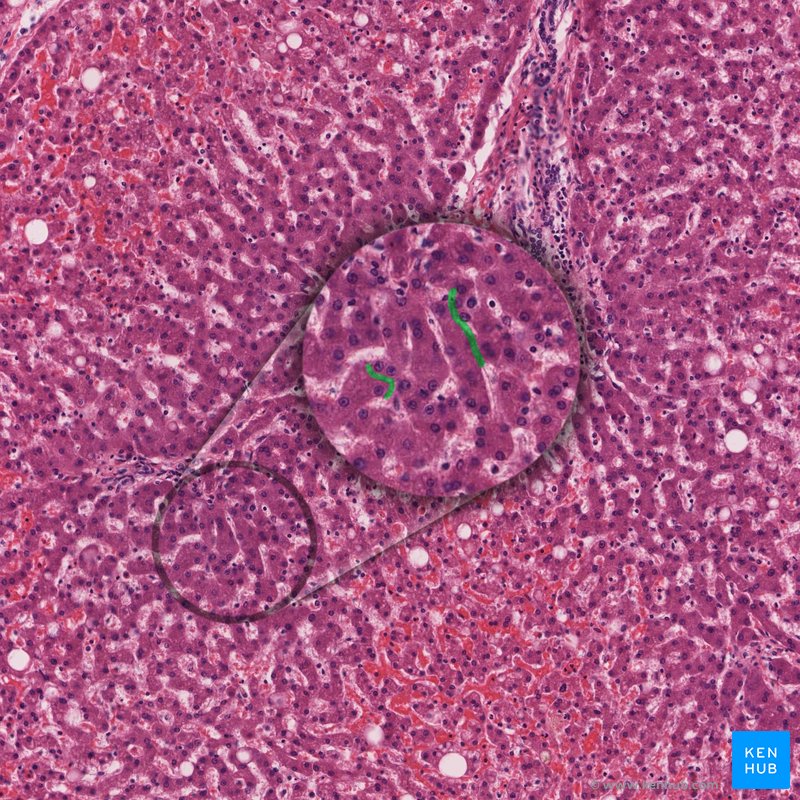

O trato biliar intrahepático é um sistema único projetado para transportar a bile dos hepatócitos para a árvore biliar extrahepática. Começa no nível do canalículo biliar (canal canalículo), que é um espaço dilatado entre os hepatócitos adjacentes. Lembre-se de que os hepatócitos poliédricos são dispostos de tal modo que suas extremidades apicais projetam-se nos sinusóides hepáticos (que eventualmente coalescem nas veias hepáticas). As bases dessas células estão voltadas para os canalículos biliares e secretam bile para esses canais. Acredita-se que as paredes dos canalículos sejam regiões modificadas das paredes dos hepatócitos contribuintes. À medida que esses canais se formam, eles seguem um caminho semelhante aos sinusóides hepáticos. No entanto, seu conteúdo flui na direção oposta.

Canalículos biliares - histologia

Os canalículos dentro de cada segmento hepático coalescem para formar os ductos segmentares. Portanto, existem oito ductos segmentares correspondentes a cada segmento funcional do fígado. Os ductos segmentares decorrentes dos segmentos II e III do fígado dão origem ao ducto hepático direito. Eles geralmente também são unidos pelo duto do segmento IV; no entanto, isso pode variar entre os pacientes. Os segmentos V a VIII contribuirão eventualmente para o ducto hepático esquerdo. No entanto, os segmentos V e VIII dão origem ao ducto setorial anterior (medial) direito, enquanto os segmentos VI e VII originam os ductos setoriais posteriores (laterais) direitos.

O ducto setorial posterior direito é mais longo que seu correspondente, e pode ser visto medialmente, atrás do ducto setorial anterior direito antes de perfurar o ducto setorial anterior direito na superfície medial para formar o ducto hepático esquerdo. Deve notar-se que o segmento hepático I (isto é, o lobo caudado) drena para o ducto hepático esquerdo, bem como para o ducto sectorial posterior direito.